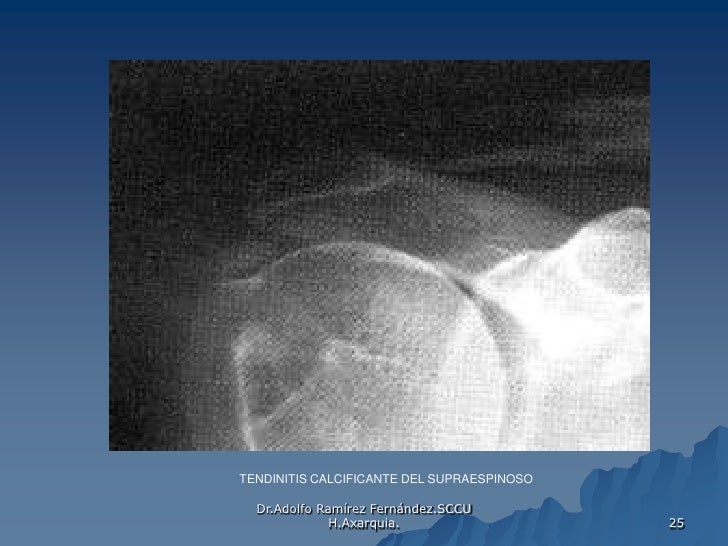

Tendinitis de hombro o supraespinoso infiltraciones | FisioOnline

Source: es.slideshare.net